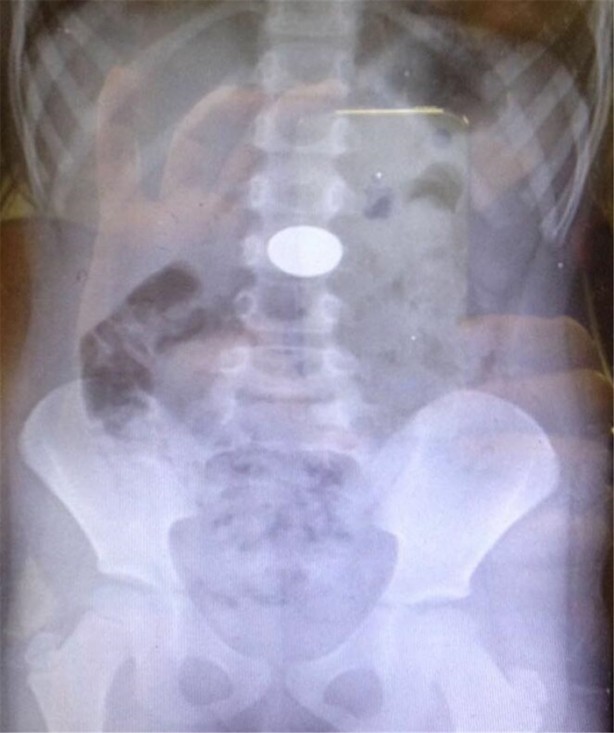

İzmir Tepecik Eğitim ve Araştırma Hastanesi Çocuk Gastroenteroloji Bölümü'nün, yabancı cisim yutan çocukların nefes ve borusu ile midelerinden çıkarttığı, anahtarlık, madeni para, saat pili, ataç, çengelli iğne ve çivi gibi objeler görenleri hayrete düşürdü.

Bu objelerden en tehlikelisinin piller olduğuna dikkat çeken Doç.Dr. Maşallah Baran, "Piller kimyasal mekanizmayla mukozayı yakıyor, özellikle yemek borusu çok duyarlı pillere, hele ki yeni takılmış bir pilse saatler içinde şahit olduğum bir kaç vaka var, yemek borusunu kömür haline getirebiliyor" dedi.